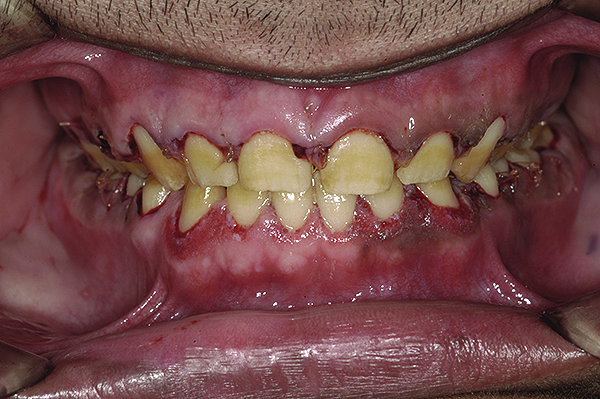

Figure 14. 1:2 retracted frontal view with provisionals in MIP.

Figure 14

After the material had set, the index was removed. A correctly fabricated index will show a thin uniform flash of excess material, which, in this case, was carefully peeled off and cut with a sharp #12 blade. The provisionals on the lower jaw were fabricated in a similar manner. Once the gross excess was removed, the patient was guided to close in MIP, with the condyles guided to CR. The occlusal contacts were then marked and adjusted until uniform contacts of equal intensity were achieved on both sides and anterior guidance was sufficient to disclude posteriors in all eccentric mandibular positions (Figure 13 and Figure 14).

At this juncture, an evaluation of the esthetics, phonetics, VDO, and all other macro and micro elements15 of smile design should be verified. Any changes—additive or subtractive—can be carried out in the patient’s mouth itself. The full-face smile photographs and close-up views were taken and evaluated. The patient was asked to “test drive” the provisionals for a few weeks and report with any feedback so that necessary corrections could be carried out. At this time, even the functional aspects can be verified, and a transcranial radiograph or a CBCT scan may be taken to verify the position of condyle in the glenoid fossa.